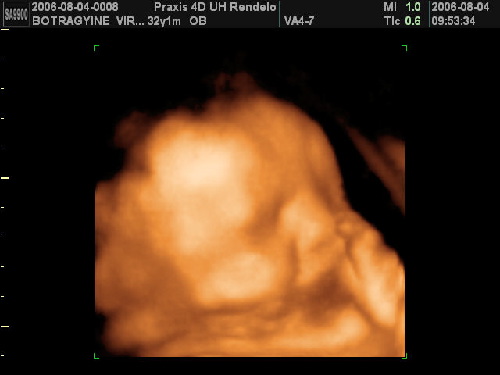

Képek pedig tüneményesek!